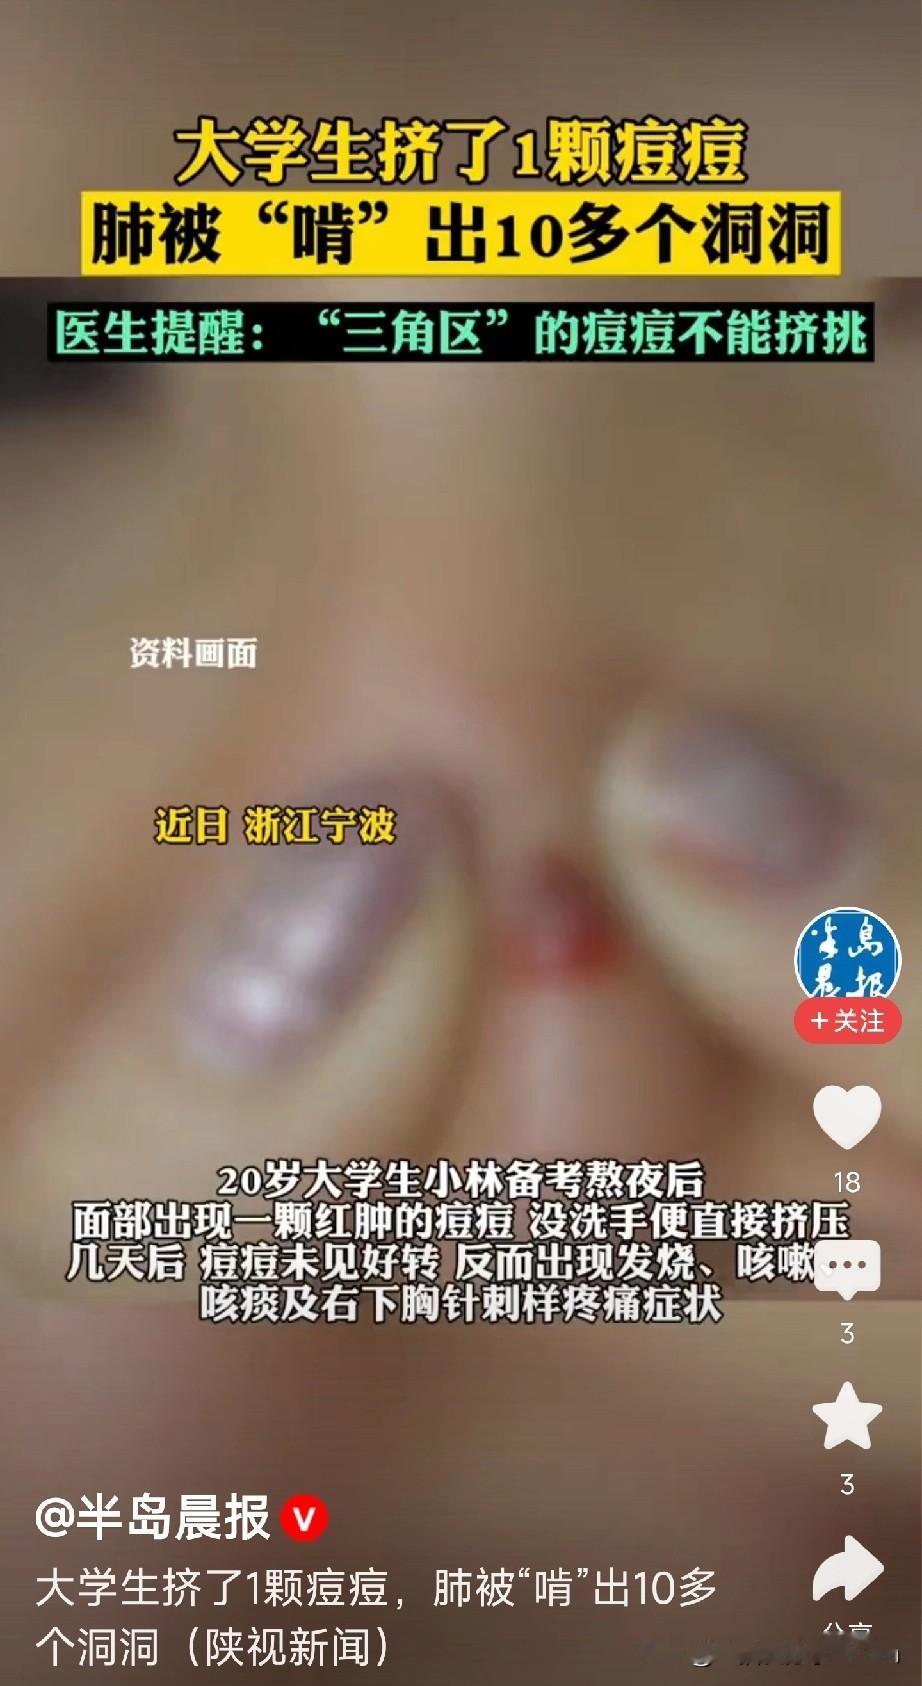

悲剧了!20岁大学生嫌脸上痘痘难看,以为挤掉能快点好,结果,痘痘依旧化脓了,甚至引发高烧,住进了ICU,医生安排CT检查,发现小林肺里有十几个空洞,部分肺组织已经坏死!网友:不知、不知道,一知吓一跳,我都不知道挤了多少个痘痘! 这事儿听着就吓人,谁能想到挤个痘痘能闹到进ICU的地步。小林这情况,医生后来解释说,是因为他挤痘痘的时候,手上的细菌顺着破损的皮肤钻进了血管,一路感染到了肺部,引发了严重的脓毒症。脸上的痘痘看着小,可位置特殊,尤其是鼻子周围那片“危险三角区”,血管直接连着大脑,一旦感染扩散,后果真能要命。 说起来,好多人都有挤痘痘的习惯。对着镜子看到那颗红红的疙瘩,总觉得手痒痒,挤完那一刻还挺有成就感。可很少有人想过,自己的手一天摸这摸那,细菌多着呢,挤的时候稍微没注意,就可能把细菌推进皮肤深层。而且挤痘痘本身就容易把毛囊挤破,让炎症更厉害,本来几天能好的痘,说不定挤完反而肿成大包,留疤都是轻的。 小林这案例算是给所有人提了个醒:脸上的痘痘真不是随便能碰的。尤其是那种又红又肿、摸着还疼的,十有八九是有炎症,这时候挤就是火上浇油。年轻人爱美心切能理解,但比起一时的痛快,还是得讲究方法。长了痘,注意清洁,饮食清淡点,实在严重就去看医生,配点药膏或者口服药,都比自己瞎折腾强。 现在好多人对皮肤问题的认知还停留在“挤挤就好”的层面,觉得医生说的“危险”是小题大做。可真等出事了才明白,身体这台机器精密着呢,一点小伤口处理不好,都可能引发连锁反应。就像小林,本来只是想让脸好看点,结果差点把命搭进去,这教训太深刻了。 各位读者你们怎么看?欢迎在评论区讨论。